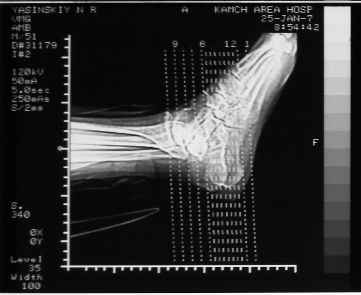

Уважаемые коллеги! Пришел на консультацию больной - "растяжение связок левого голеностопного сустава" полтора месяца назад, поскольку был в морях, на ногу не наступал. Снимки и КТ - в приложении.

Кликните для загрузки файла ПА (6).jpg

34KB (35779 bytes)